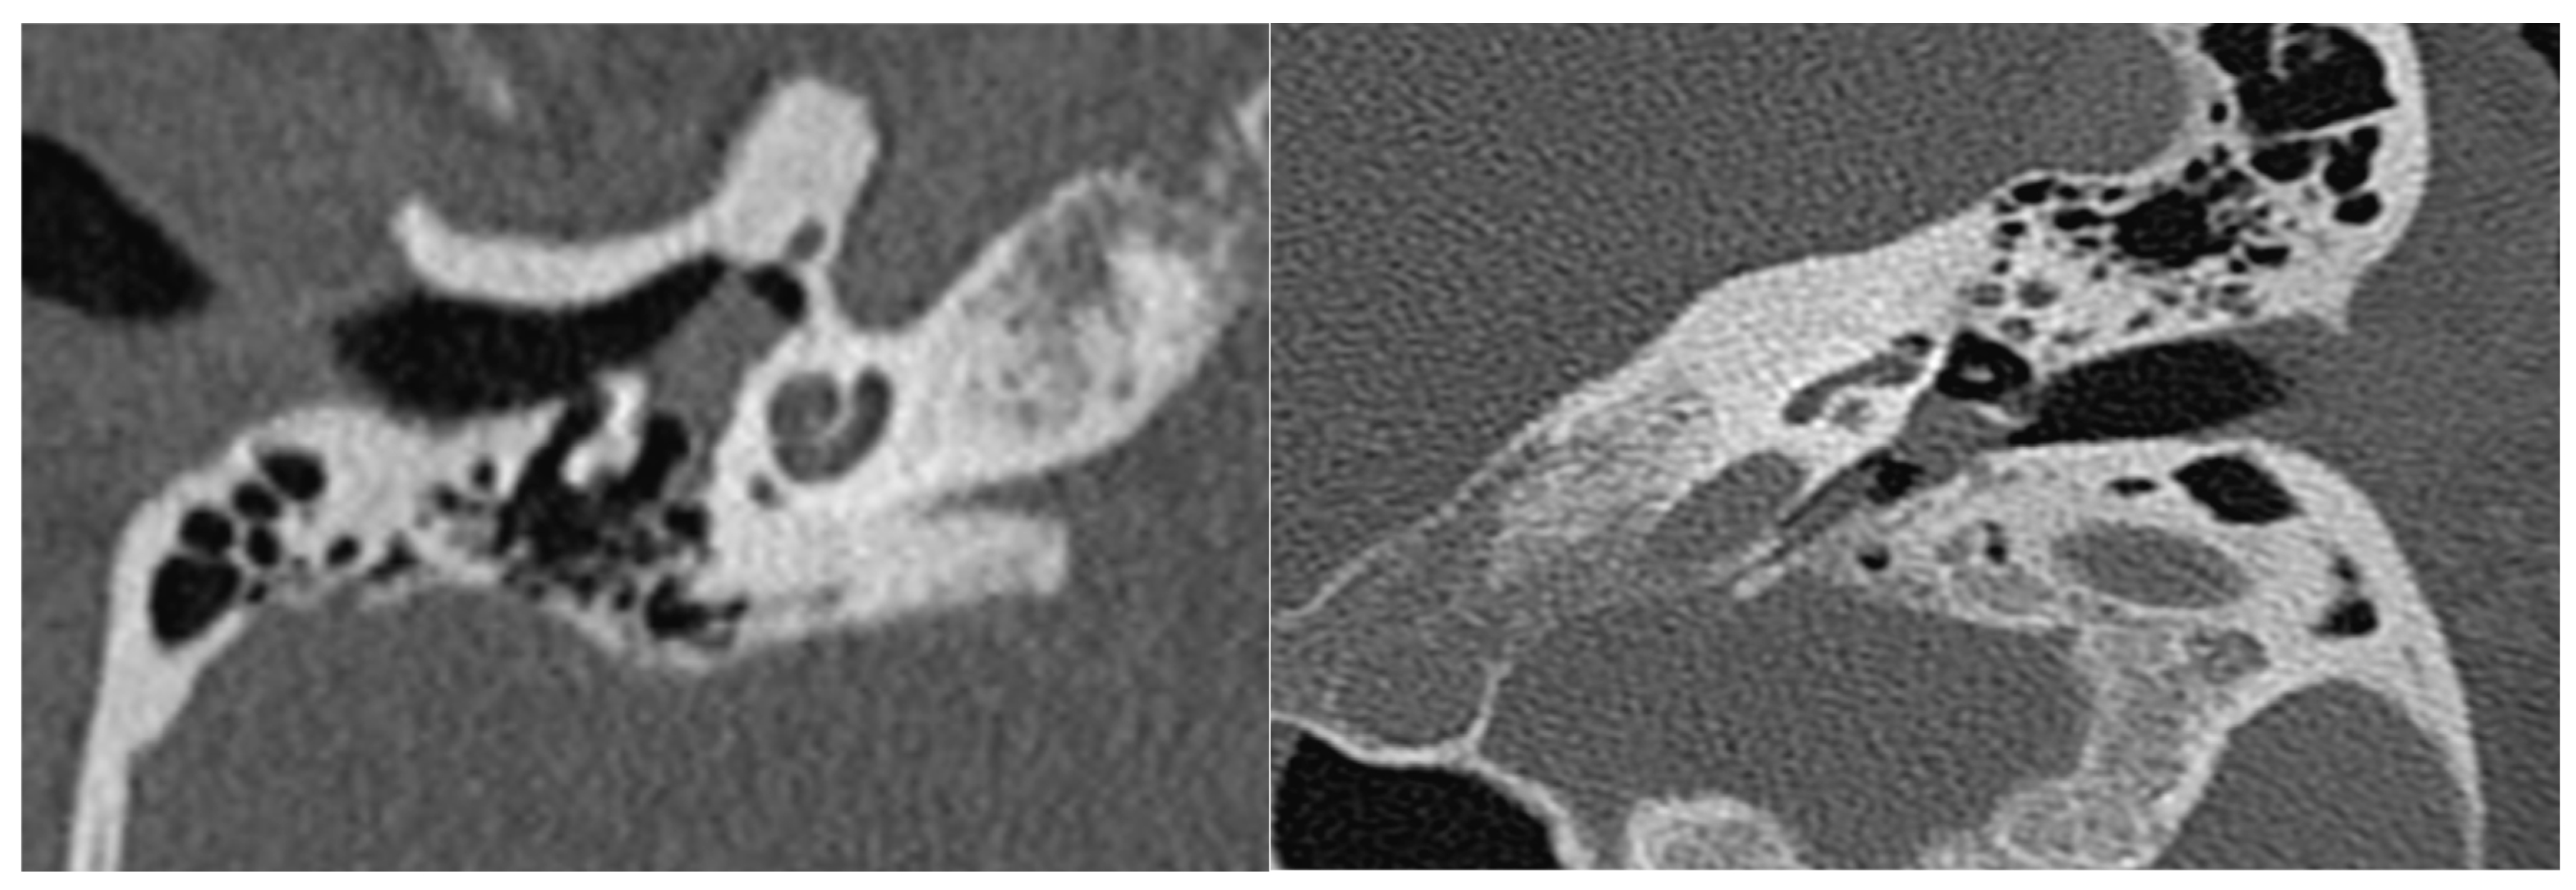

| A | Tumors limited to the middle ear cleft |

| B | Tumors limited to tympanomastoid compartment of the temporal bone |

| B | Tumors limited to the tympanomastoid compartment of the temporal bone |

| B1 | Tumor filling the middle ear cleft with extension into the hypotympanum and tympanic sinus |

| B2 | Tumor filling the middle ear cleft, extending into the mastoid and medially to the mastoid segment of the facial nerve |

| B3 | Tumor filling the middle ear cleft, extending into the mastoid with erosion of carotid canal |